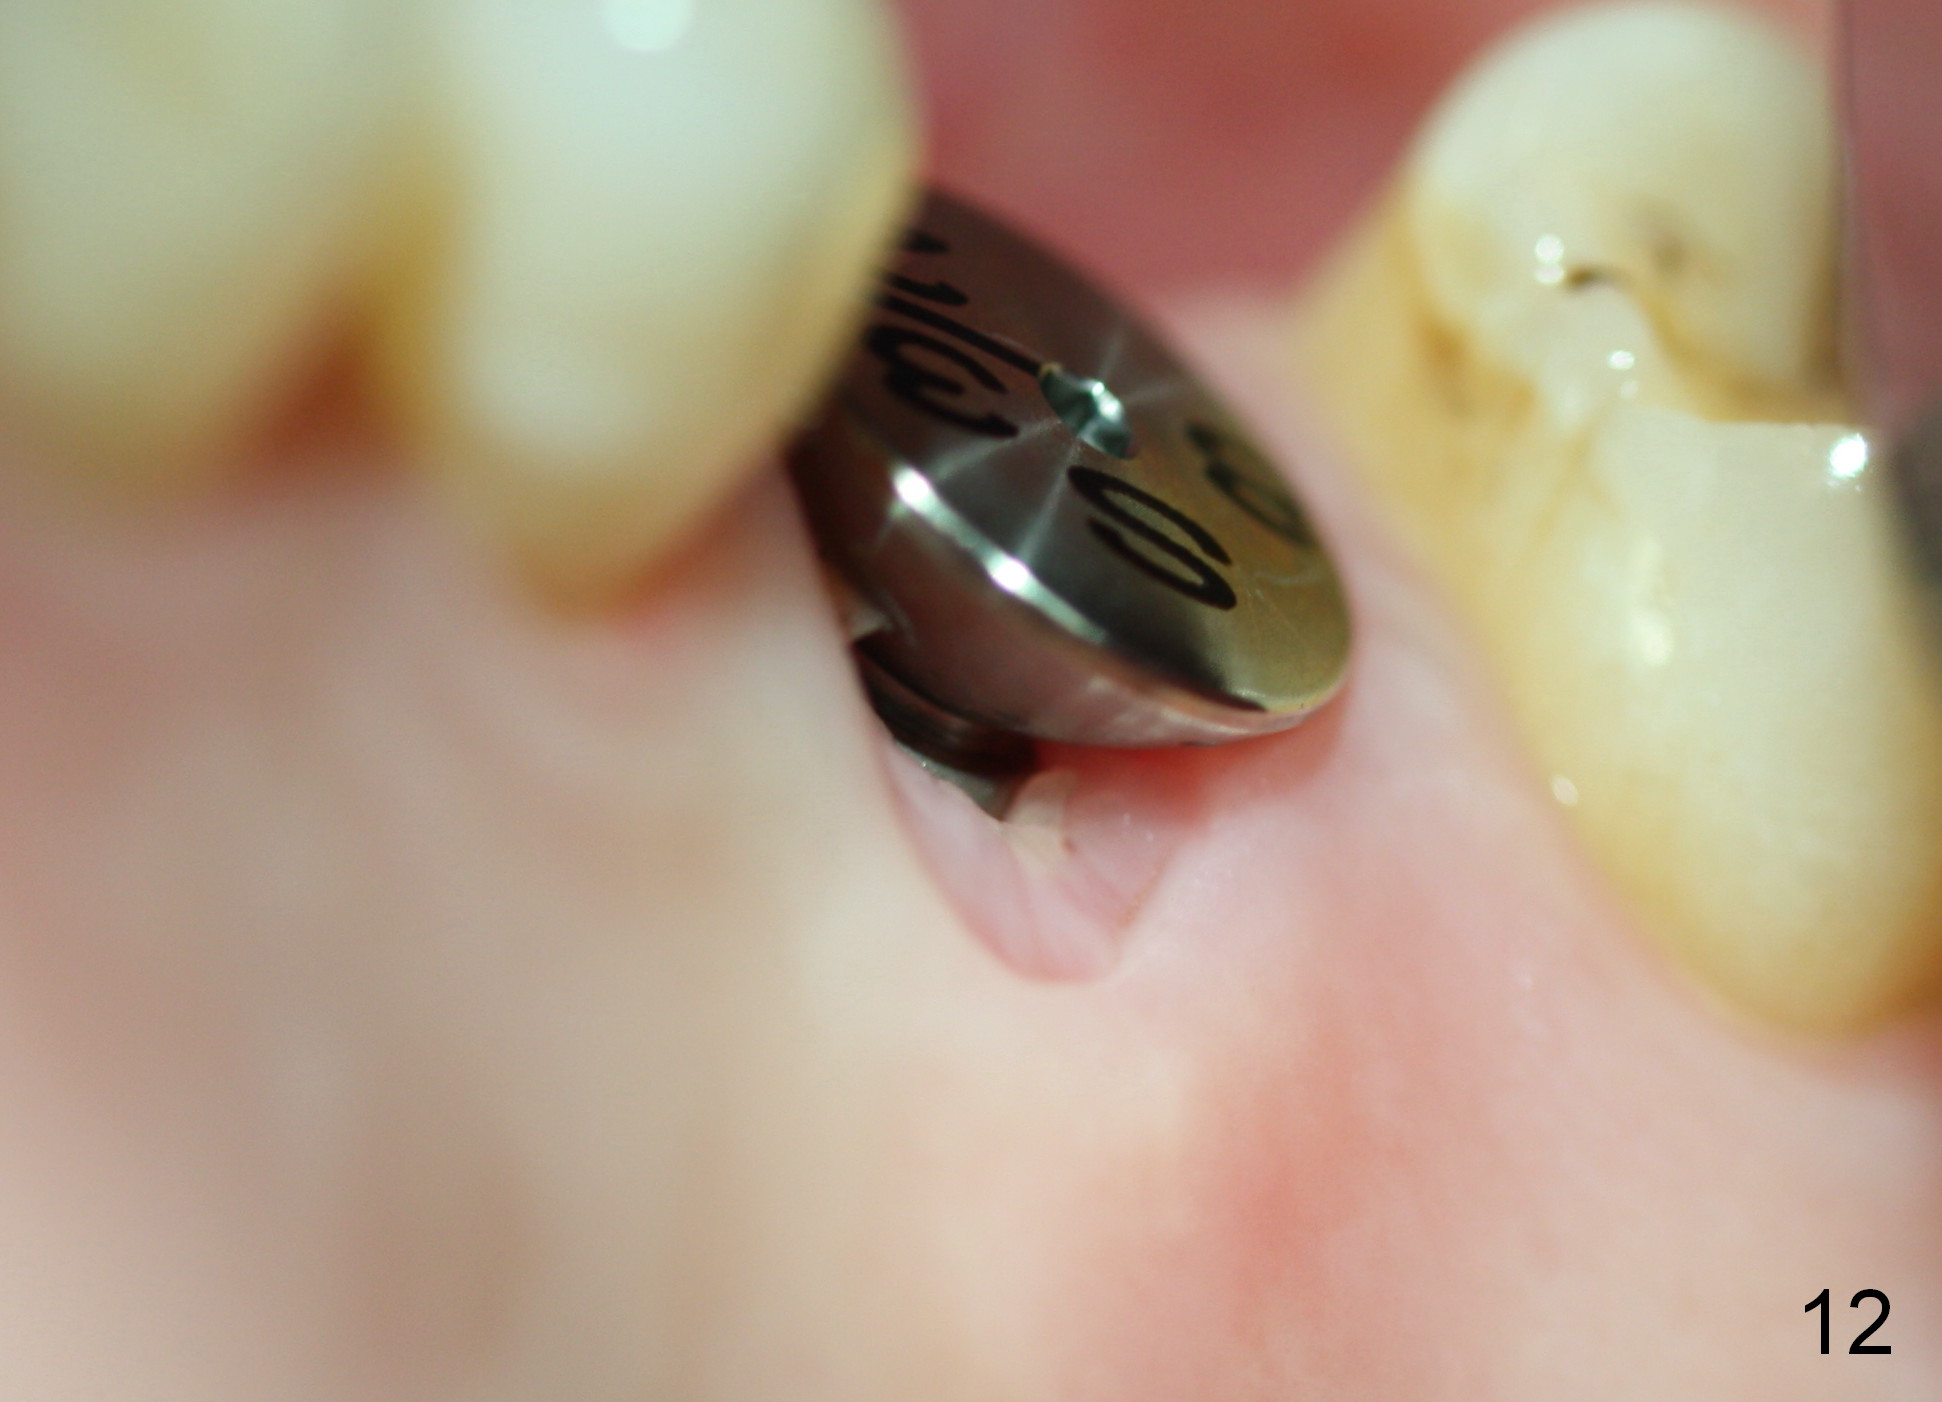

A 45-year-old man has lost the tooth #14 for a while (Fig.1); bone height is 5.4 mm. An extra wide and short implant is planned. Torus palatinus is large, suggesting that bone density should be high. A 6 mm tissue punch is chosen, but it is placed more palatal. If it were placed in the middle of the ridge, there would be no buccal keratinized gingiva (incision may avoid this issue). Additionally, the buccal portion of punch is made incomplete so that there is pedicle on the buccal side when the flap is raised (Fig.4,8: F). It is expected that the excess portion of keratinized tissue will form thick gingiva buccally. Osteotomy proves that bone is dense (Fig.2 (4.5x11 mm tap). Typical sinus lift is finished with placement of 6.4x6 mm (extra wide) bone-level implant (Fig.3, >55 Ncm). Following further torque, Fig.4 shows that the implant (I) is sub-gingival (<). Bitewings are taken to confirm that the implant plateau is at the crestal level (Fig.5,6 ^). PA shows sinus lift (Fig.7 *). The lingual aspect of the implant and healing abutment (H) is further bone grafted and covered by collagen dressing (Fig.8 *). The wound is protected with perio dressing. When the latter dislodges 7 days postop, the collagen dressing and bone graft are lost as well (Fig.10), while the buccal flap remains vital (Fig.9). The lingual exposed plateau should be able to heal normal. The collagen dressing should have been fixed in place by suture or as simple as a dental floss. There is mild nasal hemorrhage 1-2 days postop, possibly related to sinus membrane perforation and inability of Collagen Dressing to cover the perforation and contain the bone graft. When the patient returns for #9 implant placement in 3 weeks postop, the buccal flap reduces in size (Fig.11 *), while the palatal wound has healed with minimal exposure of the implant (Fig.12). Sinus graft remains in place 3 months postop (Fig.13); the buccal flap appears to have incorporated into a part of the gingiva (Fig.14). The bone density of the sinus lift appears to increase 10 days later when an abutment is placed (Fig.15 *). Although oral hygiene is pristine, there is apparent crestal bone resorption 12 months (Fig.16) and 20 months (Fig.17) post cementation, probably due to unfavorable crown/implant ratio and bruxism as well as pre-implantation bone loss (Fig.18,19). In contrast, an immediate implant in the same patient avoids pre- or post-implantation bone loss. In fact both the soft (Fig.20) and hard (Fig.21) tissues remain healthy 2 years 8 months post cementation. The sinus lift remains 3 years 8 months post cementation (Fig.22), while the crestal bone loss persists. The patients keeps complains of food impaction distal associated with bad smell 4 years 1 month post cementation. In fact the distal proximal contact is within normal limit. The bad smell is probably due to crestal bone loss (Fig.23 (pan), 24 (CT) *) and periimplantitis. Bone graft, PRF and Cytoplast membrane will be needed and fixed in place with long healing screw. When the patient returns for crown redo, he also reveals floss related gingival hemorrhage. There is pain associated with palatal sulcus probing with light gingiva erythema. Review of CT coronal section shows possible palatal (Fig.25 P) bone loss (*).